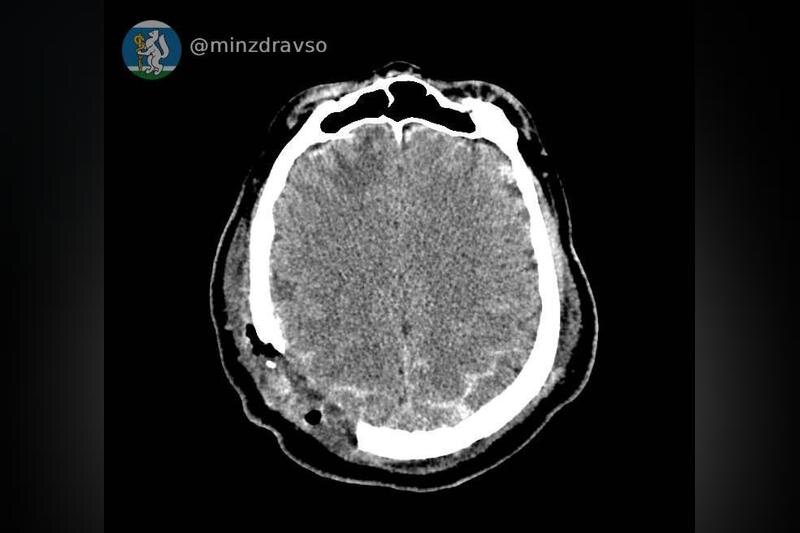

В Серове 57-летний мужчина получил тяжелую травму от стрелы строительного крана, которая пробила ему череп. Об этом сообщает пресс-служба свердловского минздрава.

В критическом состоянии пациента доставили в единственное на севере региона отделение скорой помощи в Серовской городской больнице. Благодаря высокоточному компьютерному томографу врачи быстро диагностировали повреждения и определили местоположение костных отломков, угрожающих жизни пациента. Реаниматологи Серовской больницы оперативно стабилизировали состояние мужчины.

Специалисты из Екатеринбурга провели телеконсультацию и подтвердили необходимость перевода пациента в межмуниципальный медицинский центр. Мужчину срочно перевезли в Городскую больницу №1 Нижнего Тагила, где его ждала бригада нейрохирургов. Операция, проведенная нейрохирургом Дмитрием Неволиным, анестезиологом-реаниматологом Аслламом Абдуевым и операционной медсестрой Ниной Дмитриевой, включала удаление костных отломков и гематом, а также восстановление целостности твердой мозговой оболочки.